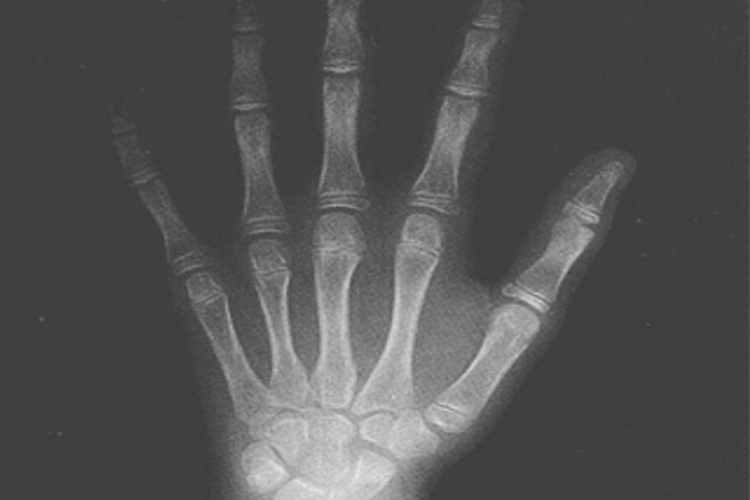

九岁男孩和女孩的骨龄测量影像与十岁测量大体相同,其影像学表现存在区别,具体如下:

九岁女孩

指骨:第2-4近端指骨远侧的滑车面出现切迹,第5近端、中间指骨骨与干骺端等宽,第3远端指骨骨骺的桡侧端已开始盖住骨干。

掌骨:第1掌骨骨骺的关节面出现凹陷,第5掌骨骨骺的尺侧、桡侧的白线为其部分掌面缘。

腕骨:钩骨的出现,三角骨远半侧增大,其钩骨面与钩骨相吻合,在其内侧可见掌面缘的白线,月骨的舟骨面和桡侧面已明显可见。